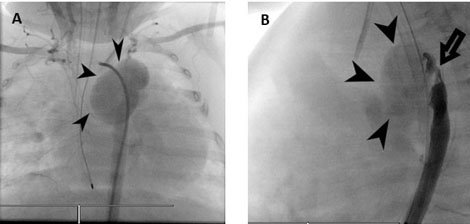

A three months old girl who was diagnosed with severe long segment COA, patent ductus arteriosus (PDA), and large mid muscular ventricular septal defect (VSD). At three weeks of age, she underwent coarctation repair with pericardial patch, PDA ligation, and pulmonary artery (PA) banding (Figure 3).

Postoperatively she was stable and echocardiogram revealed mild residual coarctation, PAB gradient 54 mmHg. Six weeks later the patient presented with respiratory distress and admitted to intensive care unit, she developed sepsis and cardiogenic shock which was not responding to supportive management. Blood cultures showed growth of Pseudomonas aeruginosa. A transthoracic echocardiography demonstrated a huge pseudoaneurysm close to the aortic arch patch (Figure 3).

Computed tomography revealed pseudoaneurysm at the surgical site distal to the origin of the left subclavian artery. There was fistulous connection to the left main pulmonary artery. The large pseudoaneurysm causes compression of the descending aorta distal to it.

Figure 3: (A) This AP view shows the huge aneurysm at the coarctation site, edges revealed by arrow head. (B) This lateral view shows the huge aneurysm at the coarctation site, edges revealed by arrow both blue arrow heads and the coarctation site seen by the yellow arrow head.